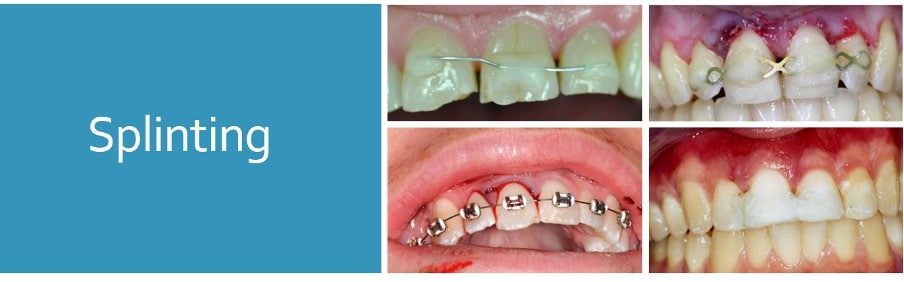

Splinting

Ideal requirements

- Secure

- Easily applied and removed

- Stabilise tooth in correct position

- Allow physiologic tooth mobility

- Allow pulp sensibility testing and endodontic access

- Allow adequate OH

- Avoid interference with occlusal movements

- Provide comfort

Types

- Composite and wire*

- Orthodontic wire and bracket*

- Fibre splints (Everstick)*

- Titanium trauma splints

- Composite splints

- Suck-down splints

- Buccal (usually)

- Flexible (0.016” SS wire)

- Passive

- One non-traumatized tooth either side of affected tooth/teeth

- Keep away from gingival margin